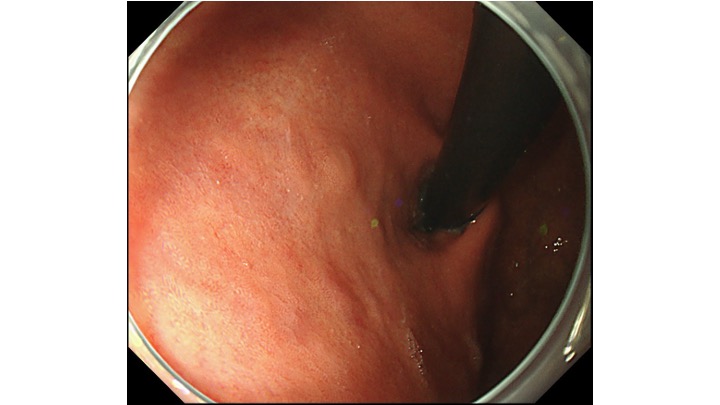

胃の上部の病変です。通常観察では、局在診断が困難な症例です。

さて、どこに病変があるでしょうか?